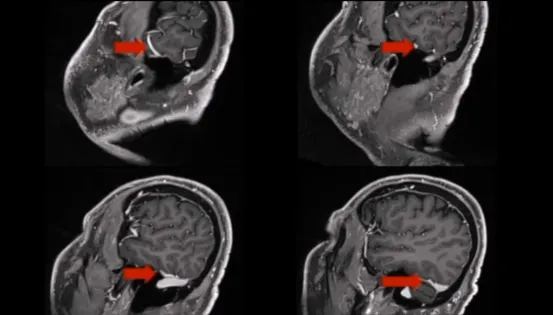

术后CT未显示任何术后并发症,术后MRI显示脑膜瘤几乎完全切除。

在术后过程中,患者出现了部分第滑车神经麻痹,向下看时伴有轻微复视,但在3个月后完全恢复,以及由于中耳炎引起的轻微听力下降,在6个月后完全解决,在随后的复查中稳定无复发。